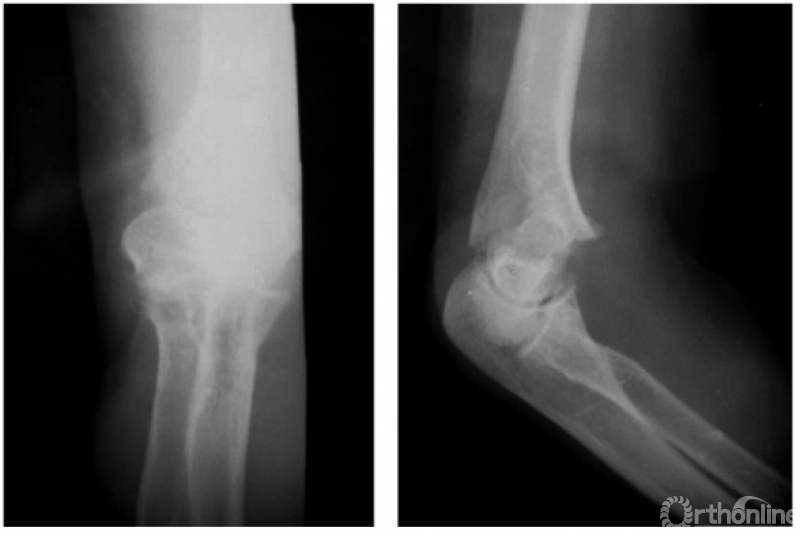

(二) 伸展型

例1:伸展型兼桡偏,即远折端向后向外移位(图2)。

图2

例2:伸展型兼尺偏,即远折端向后、向内移位(图3)。

图3